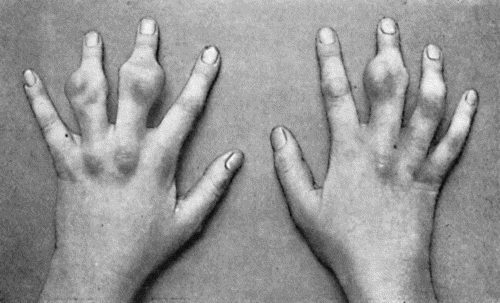

| 48. | Zanthoma of Hands | 188 |

| 142. | Multiple Chondromas of Phalanges and Metacarpals | 488 |

| 143. | Skiagram of Multiple Chondromas | 489 |

| 144. | Multiple Chondromas in Hand | 490 |